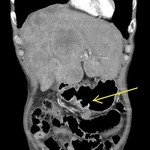

[画像診断]うっ血肝のCT所見について 2010-09-15